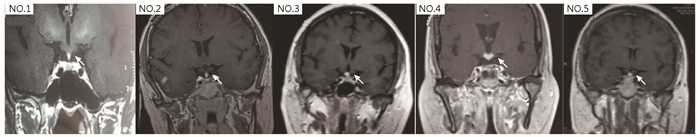

RNF216基因突变相关Gordon Holmes综合征的临床特征、基因分析及文献回顾

陈美平, 阳洪波, 潘慧, 冯逢, 朱以诚, 朱惠娟

2023, 2(3): 337-345. DOI: 10.12376/j.issn.2097-0501.2023.03.004